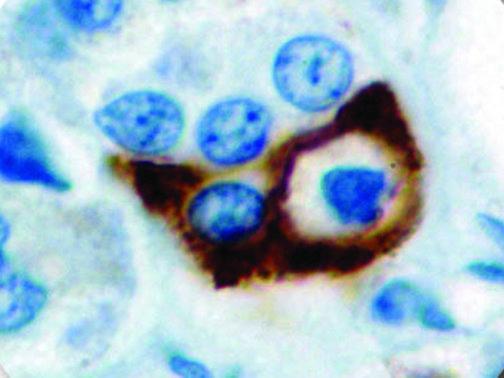

It is the ICU physician who is most likely to witness one of the deadliest manifestations of the abnormal immunological response, the cytokine storm syndrome (CSS). This response is also referred to by some as the cytokine release syndrome (CRS). CSS is characterized by continuous activation and expansion of macrophage and lymphocyte populations, which secrete large amounts of cytokines, causing the cytokine storm. This massive cytokine release is akin to hemophagocytic lymphohistiocytosis (HLH) disease, a syndrome characterized by initial unchecked and persistent activation of cytotoxic T lymphocytes and NK cells.

Clinical and laboratory manifestations of HLH include fever, enlarged liver and/or spleen, neurologic dysfunction, coagulopathy, liver dysfunction, cytopenias (i.e., low levels of erythrocytes, leukocytes, and/or platelets), hypertriglyceridemia, hyperferritinemia, hemophagocytosis, and eventually diminished NK cell activity as the immune system becomes progressively paralyzed. HLH can be familial (primary HLH) or secondary to another disease process (sHLH), such as rheumatic disease, in which it is referred to as macrophage activation syndrome (MAS, characterized by elevated ferritin).